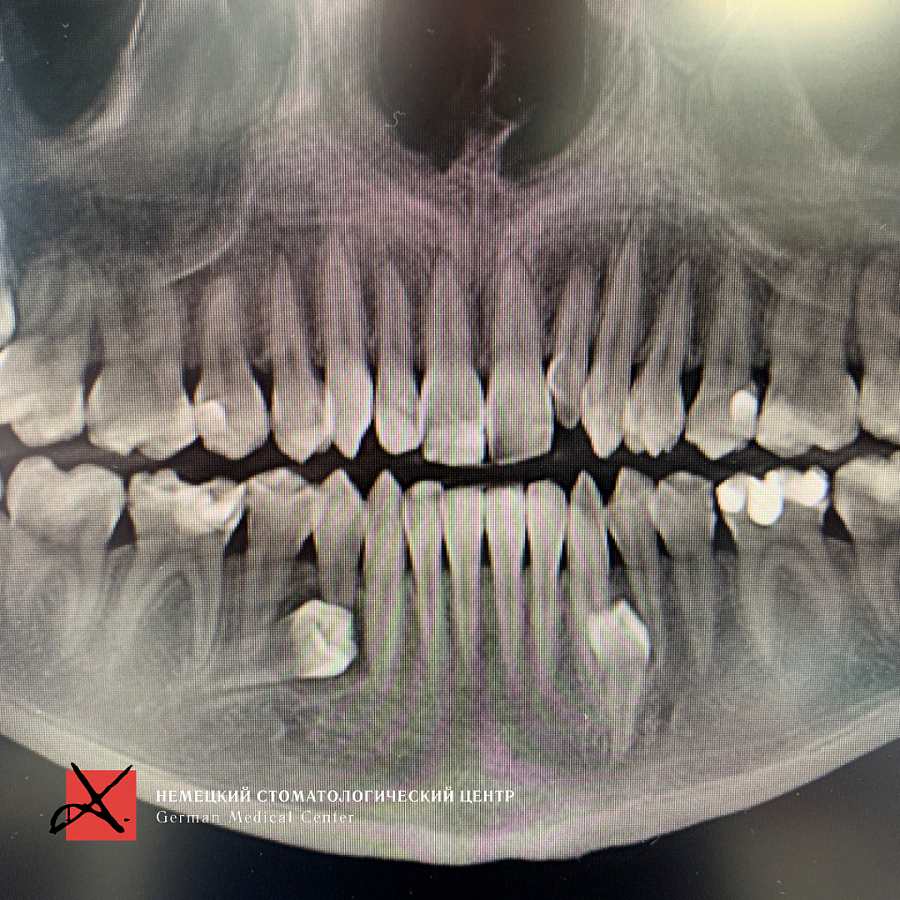

Пациент направлен врачом-ортодонтом с целью удаления ретинированных дистопированных зубов. У пациента аномалия: лишние зубы в передне-боковых отделах.

Зубы были удалены через окошко в кости, сделанное изнутри полости рта со стороны языка. Заживление прошло отлично, пациент ни на что не жалуется, соседние зубы не были повреждены.